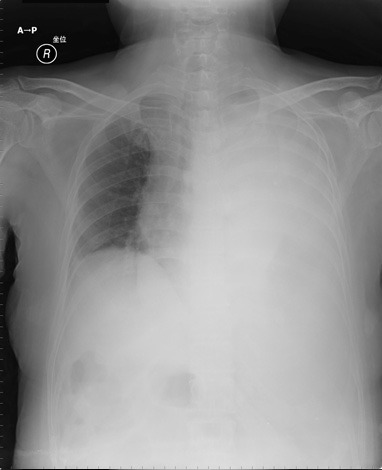

全身倦怠感と左側の大量胸水貯留を主訴に紹介来院。鼻腔より2L/分の酸素吸入にてSpO2は98%に保たれ、安定した状態にあった。

入院時の心電図は全体にlow voltageである。これは左胸腔全体に貯留した胸水の影響である(図1)。

図1